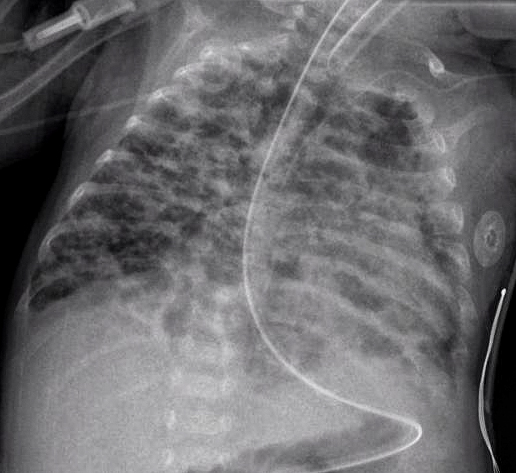

Бронхолегочная дисплазия – самое частое

хроническое заболевание легких у недоношенных новорожденных детей с критично

низкой массой тела (до 1 кг при рождении). Оно связано с незрелостью легочных

тканей, токсичным воздействием кислорода при искусственной вентиляции легких и

рядом других факторов. В настоящее время выделяют легкую, среднюю и тяжелую

степени болезни. Первоначальная задача врачей – подобрать лечение, которое

снизит риск развития серьезных форм недуга.